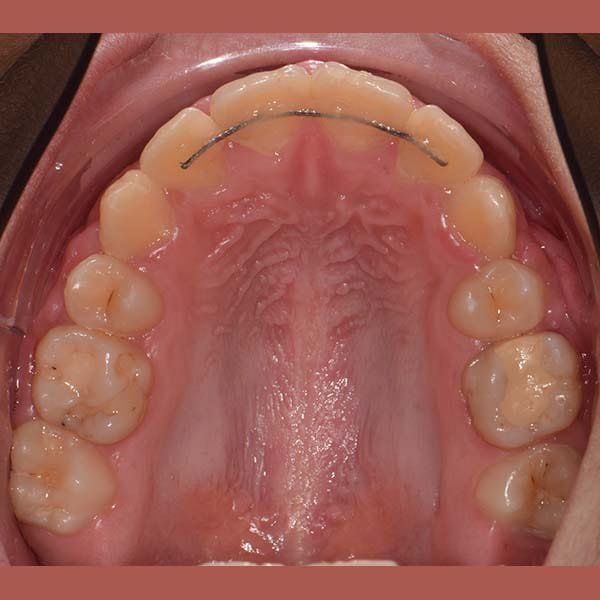

AFTER